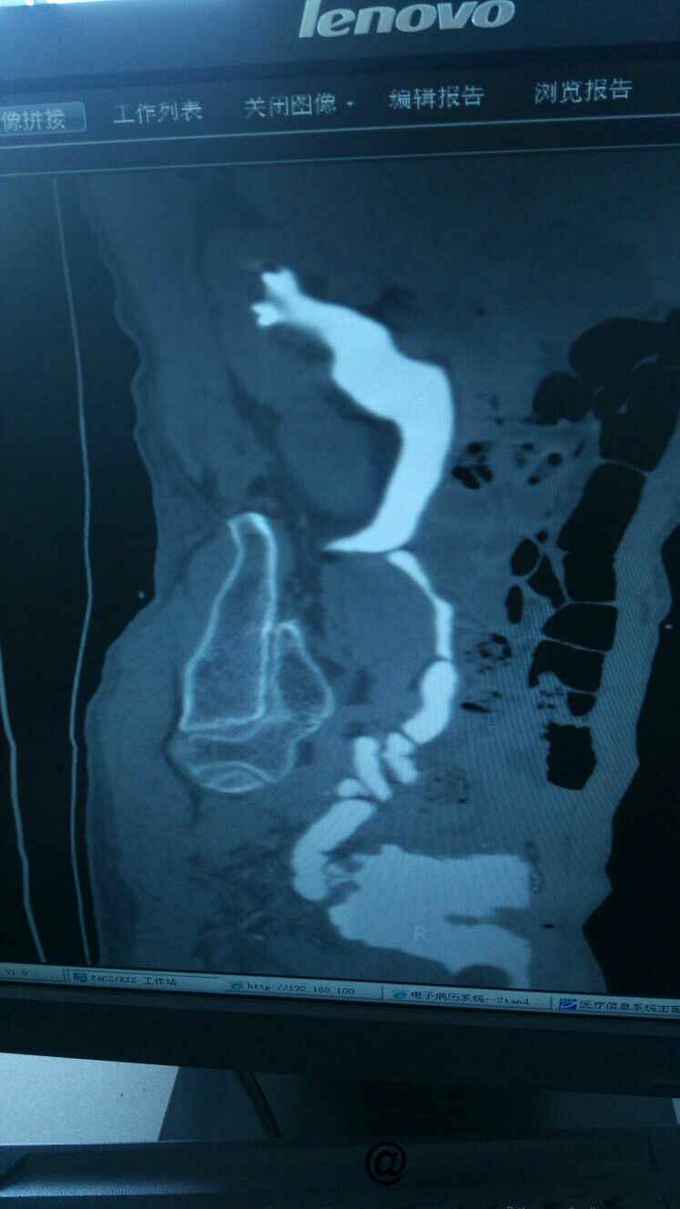

查膀胱镜发现后尿道狭窄,无法进入膀胱。 尿道造影:尿道狭窄,输尿管逆流。嘱咐病人排尿时,膀胱内尿液减少,进入输尿管,肾盂。 肾功能正常。

诊断:尿道狭窄,输尿管逆流 治疗:输尿管镜下探查,见尿道狭窄,膀胱内景清晰,广泛房小梁形成,右侧膀胱后壁可见广口凹陷,输尿管镜置入,可向上探查,实为输尿管,管腔宽大,输尿管镜进出自如,未见占位病变,向膀胱内置入导丝,沿着导丝留置导尿管扩张尿道。